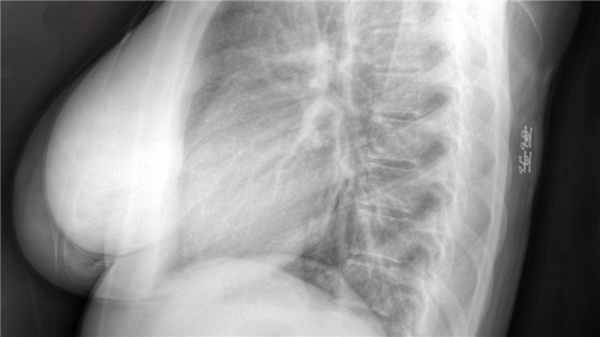

РКТ грудного отдела:

- усиление грудного кифоза

- тела позвонков остеопорозны, высота снижена, деформация позвонков Th4, Th5, Th6, L1 по типу "бабочки"

- в теле Th7 позвонка - гиподенсные включения по типу "вакуум-эффекта"

- субхондральный склероз и узурация замыкательных пластинок (грыжи Шморли)

- позвоночный канал имеет нормальный передне-задний размер

- высота межпозвонковых дисков снижена

- на уровне диска Th7-Th8 - участок сужения спинного мозга на 1/3 общего диаметра

- артроз рёберно-позвоночных и рёберно-поперечных суставов